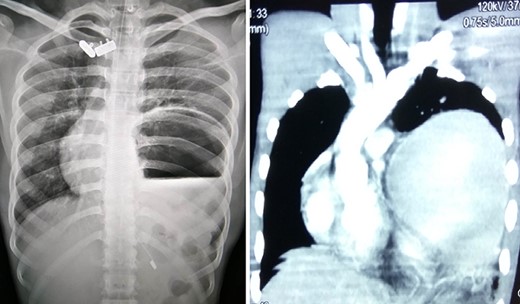

A 75-year-old male presented to the emergency with severe pain in the epigastrium, multiple episodes of non-bilious vomiting and epigastric fullness for the past 2 days. There was no history of weight loss, anorexia, hematemesis or early satiety. Eight months before, he had similar complain (resolved spontaneously), was admitted, and evaluated with upper GI endoscopy and CT abdomen, with normal findings. On examination, patient was tachycardic but normal blood pressure. There was epigastric fullness with mild tenderness. Blood investigations revealed normal hemoglobin, but leukocytosis (16 000 cells/mm3). The renal function test and serum chemistry were normal. Chest X-ray was done, which showed elevated left hemi-diaphragm with large gastric shadow beneath it (Fig. 3). In view of recurring symptoms, chronic gastric volvulus was considered as differentials. On further imaging with CT abdomen, it confirmed gastric volvulus. Patient was taken up for emergency laparotomy. Intraoperatively, organo-axial gastric volvulus secondary to diaphragmatic eventration was seen. It was de-rotated and fixation of the stomach was performed by double, non-draining tube gastrostomy (at two points, body and antrum) with sham gastrojejunostomy to prevent recurrence (Fig. 3). No attempt at the plication of eventration was done due to the technical difficulty, splenic capsular tear and secured stomach fixation. The patient did well postoperatively and was discharged on Day 8. At 38 months follow-up, the patient is asymptomatic.

Chronic gastric volvulus, showing raised left hemi-diaphragm in chest X-ray, with intraoperative placement of double gastrostomy tube for fixation.